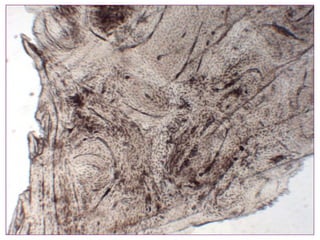

El documento describe diferentes aspectos de la histología del cartílago y el hueso, incluyendo las estructuras del cartílago como condroblastos, matriz y lagunas, y las estructuras óseas como conductos de Havers, osteoblastos y osteoclastos. También describe las etapas de la osificación endocondral, el proceso por el cual el cartílago se transforma en hueso, incluyendo las zonas de cartílago en reposo, proliferación, hipertrofia, erosión y osificación.